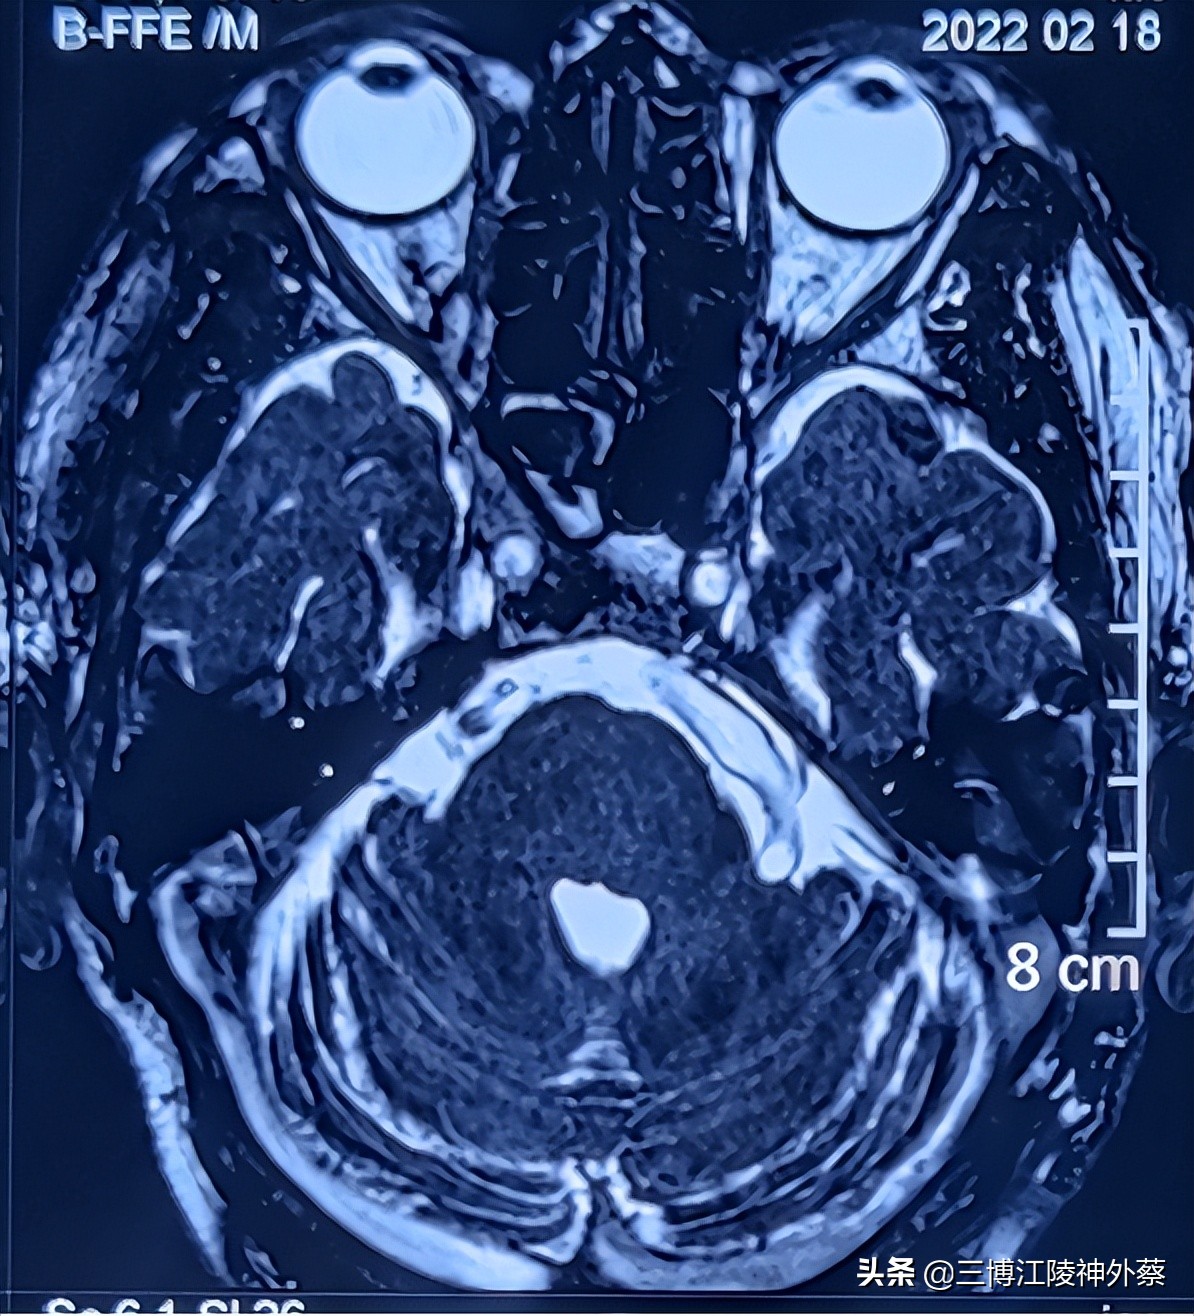

·辅助检查MRI提示:双侧椎动脉、基底动脉扩张延长症,且走行于左侧三叉神经区域,左侧三叉神经未见明显显示,考虑椎基动脉压迫左侧三叉神经。

椎动脉、基底动脉扩张延长症,且走行于左侧三叉神经区域